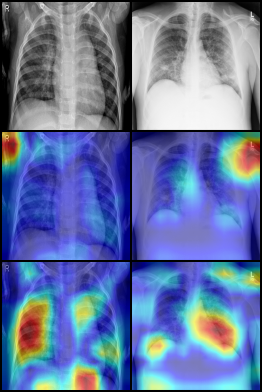

For the covid-qu-Ex dataset, we trained the network with hyperparameters λ=5𝜆5\lambda=5, ρ=0.25%𝜌percent0.25\rho=0.25\%, 2 downsampling steps in the attention network, and 5 downsampling steps in the replacement network. We used a learning rate of 21042superscript1042\cdot 10^{-4} for both the lens and classifier. As there is no validation set without shortcuts for covid-qu-Ex, we evaluated the effectiveness of the lens in identifying shortcuts using GradCAM [22]. Figure 4 shows the GradCAM images for all three classes and both trained networks. From these experiments, we made several observations. First, without the lens, the network predominantly focused on areas in the corners of the images, mostly in areas with text. Second, with the attention lens, the network focused on more relevant sections of the image, including the lungs. Our proposed approach not only explains shortcuts but also corrects them, as shown in Fig. 5, where highly localized shortcuts such as markers and text are removed.

Refer to caption

(a) Normal

(b) COVID

(c) Pneumonia

Figure 4: GradCAM images showing network attention when training on the covid-qu-Ex dataset. Row 1 is the input image from the validation set. Row 2 is the classifier attention of a network trained without, and Row 3 with our proposed model.